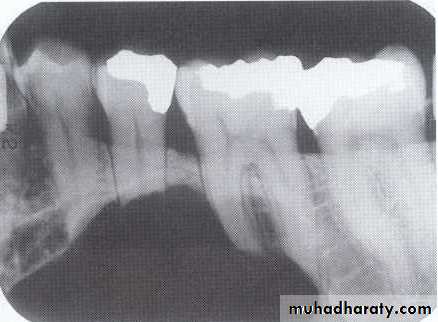

Dentigerous CystIt forms around the crown of an unerupted or supernumerary tooth at CEJ.

Some dentigerous cysts are eccentric, developing from the lateral aspect of the follicle so that they occupy an area beside the crown instead of above the crown.

It displace and resorb adjacent teeth.

It commonly displaces the associated tooth

in an apical direction.